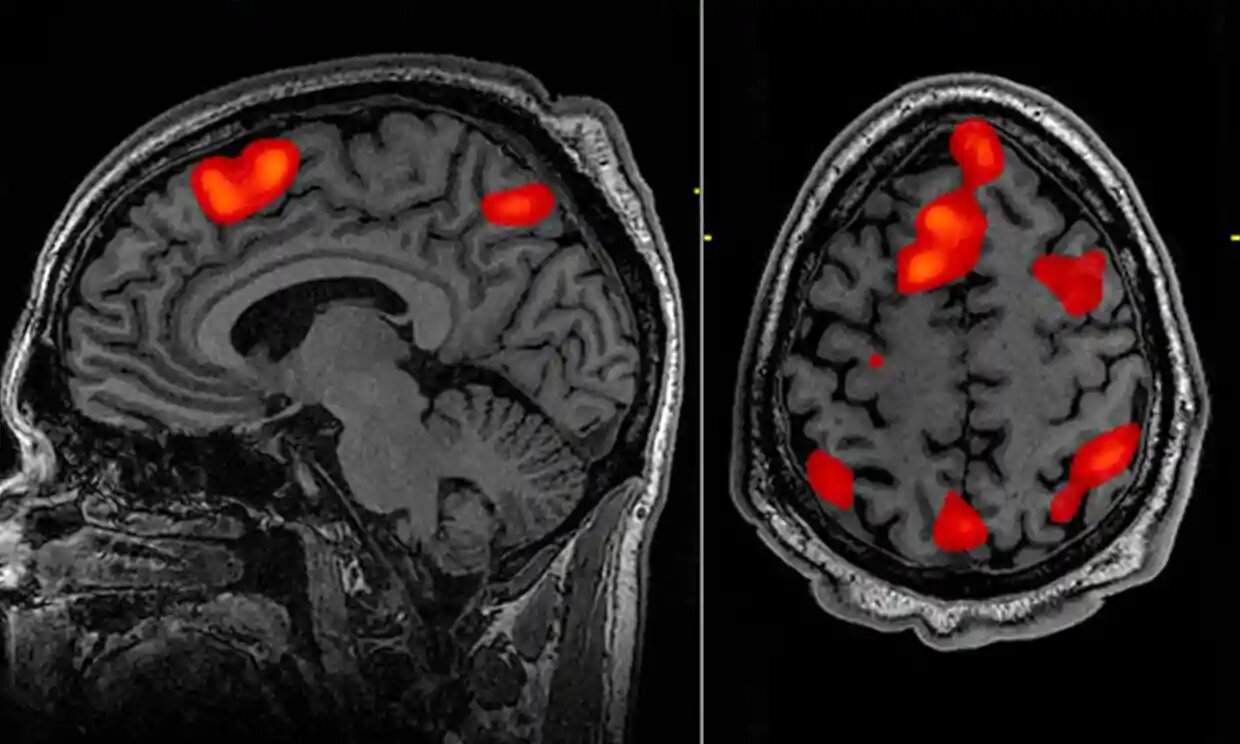

ALBAWABA – Scientists have developed an Artificial Intelligence-powered decoder that can translate brain activity into a continuous stream of text so that non-invasive mind-reading AI can read your thoughts with the help of using only fMRI scan data technology and hardware.

The mind-reading AI decoder could reconstruct speech using fMRI scan data. Photograph: John Graner